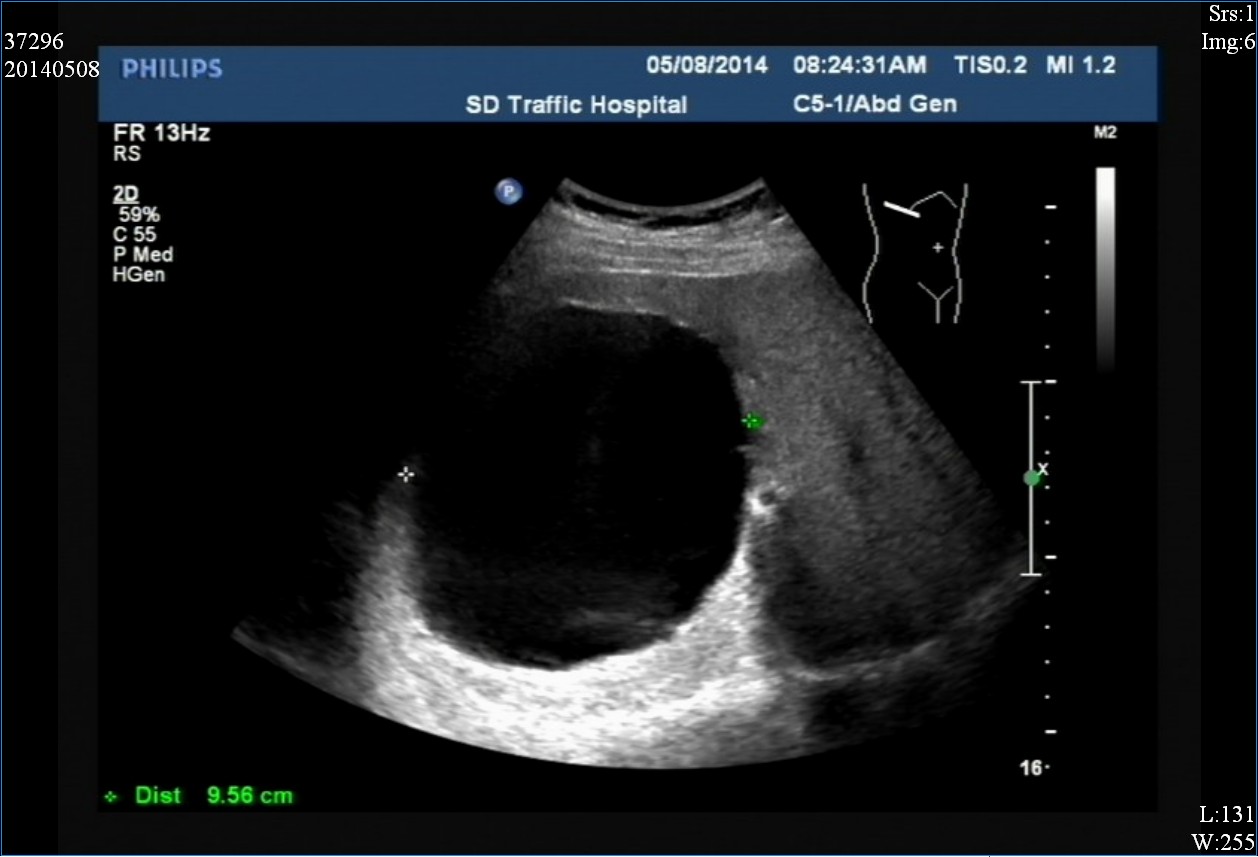

二、卵巢

卵巢囊肿是女性十分常见的一种囊肿,多见于生殖期女性,多数与内分泌系统、环境因素、不良的生活习惯、家族病史等导致。既然那么常见吗,为何还要引起警惕呢?因为,卵巢囊肿也分两种情况:生理性囊肿和病理性囊肿。

①生理性卵巢囊肿:生理性囊肿多数因女性月经期间的雌激素水平高低影响有关,主要为黄体囊肿和滤泡囊肿。生理性囊肿一般无需处理,但是如果直径大于5厘米,且出现了不适症状,需要及时就医,由医生严格评估是否需要手术切除。

巨大的卵巢囊肿

②病理性囊肿:由于生理性囊肿多因月经期间的雌激素影响,因此它的出现与月经期有关。但是如果超过3个月的月经期,囊肿仍未消失甚至有变大的迹象,那么要考虑为病理性囊肿。病理性囊肿如果再合并以下4个条件,则应及时切除:

Ⅰ、直径大于5厘米,持续半年不消失或有长大趋势;

Ⅱ、直径大于6厘米,应直接切除并送病理;

Ⅲ、如果B超检查发现囊肿为实性,则不论大小一律切除;

Ⅳ、绝经后的女性如果出现卵巢囊肿,多考虑为恶性的卵巢癌,应直接切除。